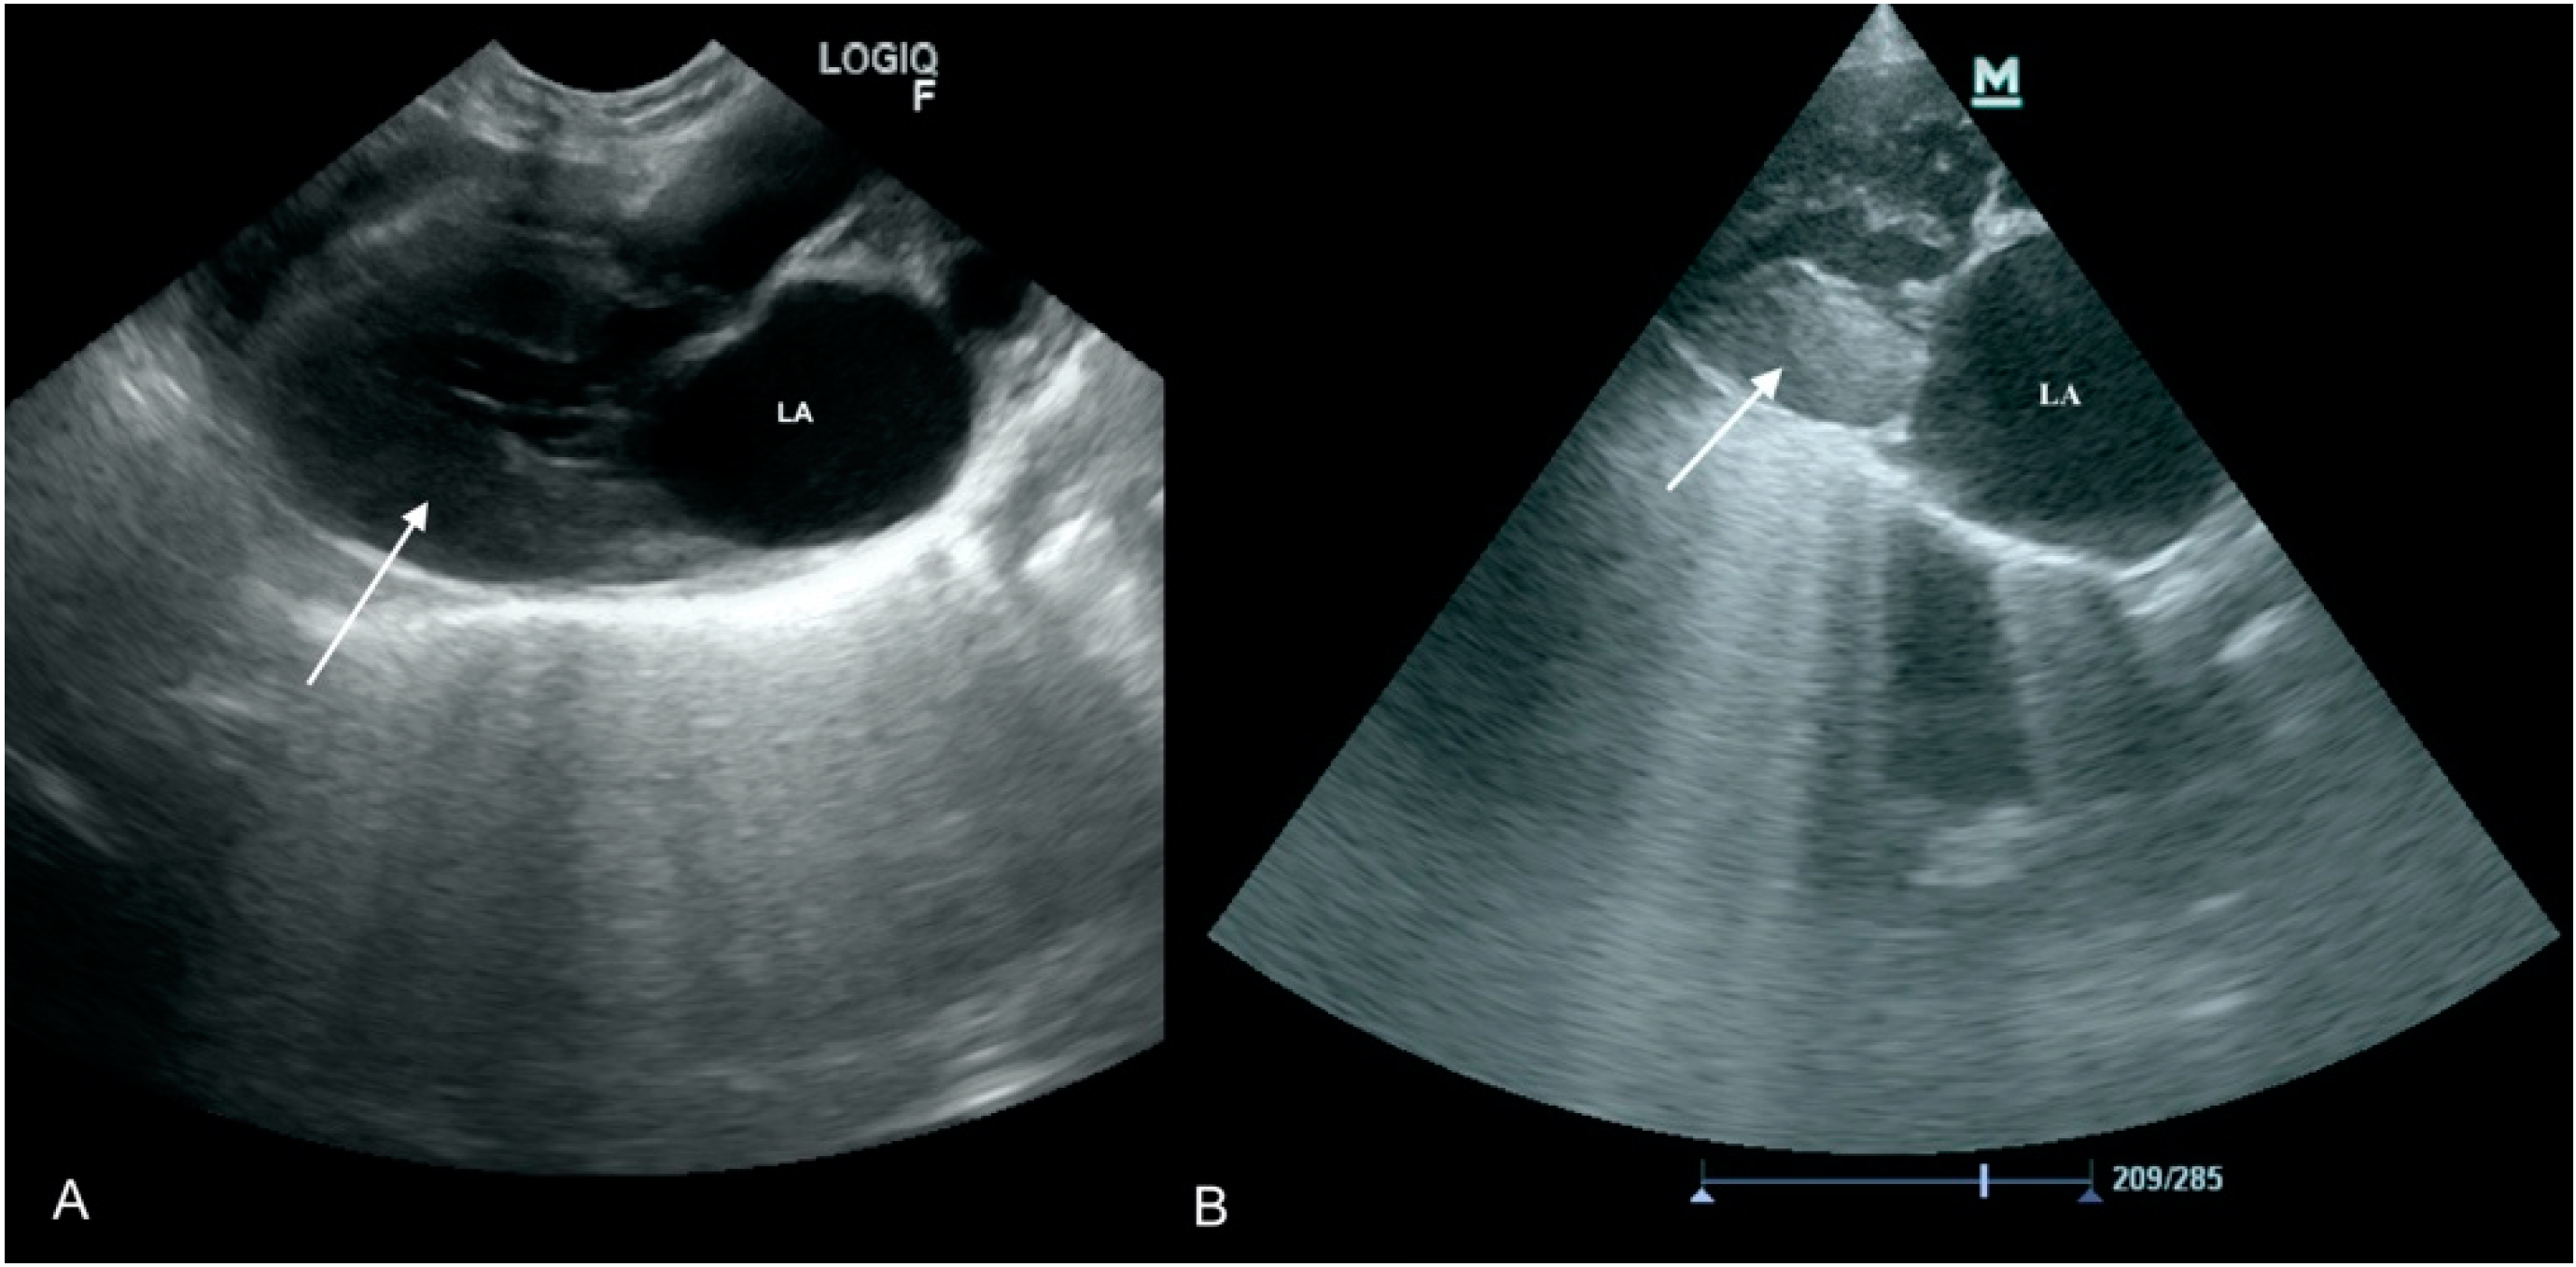

3.3. Case No. 3